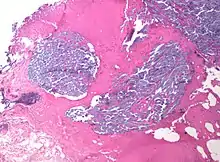

In medicine, desmoplasia is the growth of fibrous connective tissue.[1] It is also called a desmoplastic reaction to emphasize that it is secondary to an insult. Desmoplasia may occur around a neoplasm, causing dense fibrosis around the tumor,[1] or scar tissue (adhesions) within the abdomen after abdominal surgery.[1]

Desmoplasia is usually only associated with malignant neoplasms, which can evoke a fibrotic response invading healthy tissue. Invasive ductal carcinomas of the breast often have a stellate appearance caused by desmoplastic formations.

Desmoplasia refers to growth of dense connective tissue or stroma.[2] This growth is characterized by low cellularity with hyalinized or sclerotic stroma and disorganized blood vessel infiltration.[3] This growth is called a desmoplastic response and occurs as result of injury or neoplasia.[2] This response is coupled with malignancy in non-cutaneous neoplasias, and with benign or malignant tumors if associated with cutaneous pathologies.[3]

A desmoplastic response is characterized by larger stromal cells with increased extracellular fibers and immunohistochemically by transformation of fibroblastic-type cells to a myofibroblastic phenotype.[2] Myofibroblastic cells in tumors are differentiated from fibroblasts for their positive staining of smooth-muscle actin (SMA).[2] Furthermore, an increase in total fibrillar collagens, fibronectins, proteoglycans, and tenascin C are distinctive of the desmoplastic stromal response in several forms of cancer.[14] Expression of tenascin C by breast cancer cells has been demonstrated to allow for metastasis to the lungs and cause the expression of tenascin C by the surrounding tumor stromal cells.[15] In addition, tenascin C is found extensively in pancreatic tumor desmoplasia as well.[16]